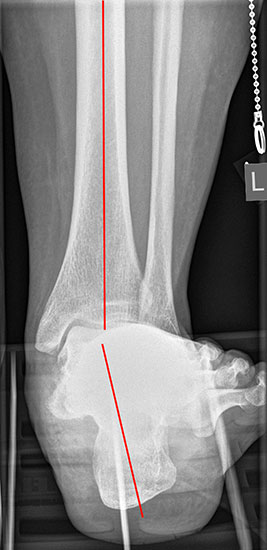

Röntgenaufnahmen des Fußes d.p., streng seitlich und schräg unter Belastung. Saltzmann Aufnahme zur Beurteilung der Rückfussachse.

Operationsplanung anhand der Röntgenaufnahmen unter Beachtung wichtiger radiologischer Landmarks wie Rückfussachse, Metatarsale I – Talushals-Achse im dp und lateralen Strahlengang (Abbildung 1 und 2).

Abbildung 1

Abbildung 2